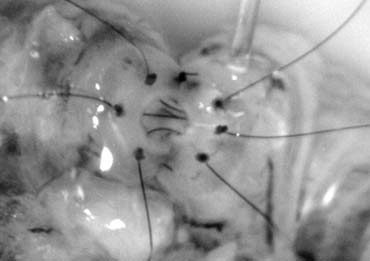

This method, also known as the triangulation technique,43 has gained increasing popularity among microsurgeons over the conventional end-to-end and end-to-side vasoepididymostomy.4,44,45,46 When the level of epididymal obstruction is clearly demarcated by the presence of markedly dilated tubules proximally and collapsed tubules distally, the site at which the anastomosis should be performed is readily apparent (Figs. 19 and 20). The vas deferens is drawn through an opening in the tunica vaginalis and secured in proximity to the potential anastomotic site in the epididymis with two to four interrupted sutures of 6-0 polypropylene placed through the vasal adventitia and the epididymal tunica (Fig. 21). Six microdots are placed on the cut surface of the vas in an identical fashion to that described for vaso-vasostomy (Fig. 22). Three 10-0 double-armed nylon sutures are placed in the epididymal tubule in a triangular fashion (Fig. 23). The needles are not pulled through but left in situ, creating a triangle of needles. A generous opening is made in the epididymal tubule in the center of the triangle created by the three needles. The three needles are then pulled through (Fig. 24). A glass slide is touched to the fluid exuding from the opening in the epididymal tubule and mixed with human tubal fluid media, covered with a cover slip and examined by the surgeon using the separate bench microscope under 400-power magnification. If sperm are present (whether motile or not) the decision is made to proceed with the anastomosis. Sperm are aspirated into micropipettes first (Fig. 25) and expressed into human tubal fluid media and sent for cryopreservation if motility is observed. After abundant sperm have been aspirated into micropipettes and cryopreserved, the six needles are passed inside out the vas deferens exiting through the six previously placed microdots in the order indicated (Fig. 26). Each pair of sutures is then sequentially tied. Tying of these sutures intussuscepts the epididymal tubule into the vas lumen (Fig. 27). This creates a water-tight closure. In addition, the flow of epididymal fluid from the epididymal tubule into the vas deferens tends to plaster the edges of the epididymal tubule against the mucosal walls of the vas deferens, further helping create a leakproof closure. The second layer of the anastomosis is completed using interrupted 9-0 nylon sutures to secure the epididymal tunica to the vasal sheath (Fig. 28).

Fig. 25. Once the presence of sperm in the epididymal tubule has been confirmed, epididymal fluid is aspirated by capillary action into micropipette for cryopreservation.